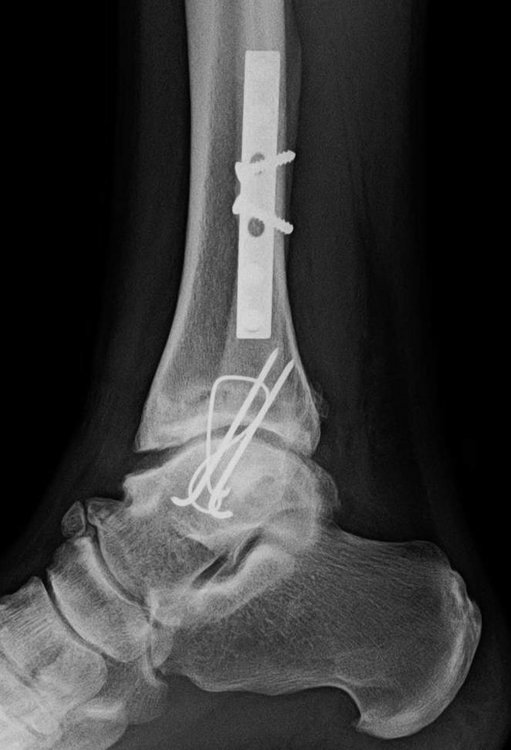

While messing around in the parking lot pre-ride, I was riding a wheelie and then lost balance and started to fall over to my right.  I could not disengage my right foot from the pedal and stupidly stuck my knee out to break the fall.  After I sat up I looked down and my right foot was turned 90 degrees outward.  Broke my ankle and fibula.  I now have a screw in the ankle and a steel plate on the fibula.

This is not to scare anyone off from using clipless pedals as I've never had an issue since.  Those Onza pedals though...turrible.  And the reason I prefer crank bros is the ease of engagement/disengagement plus the float which is easier on the knees.